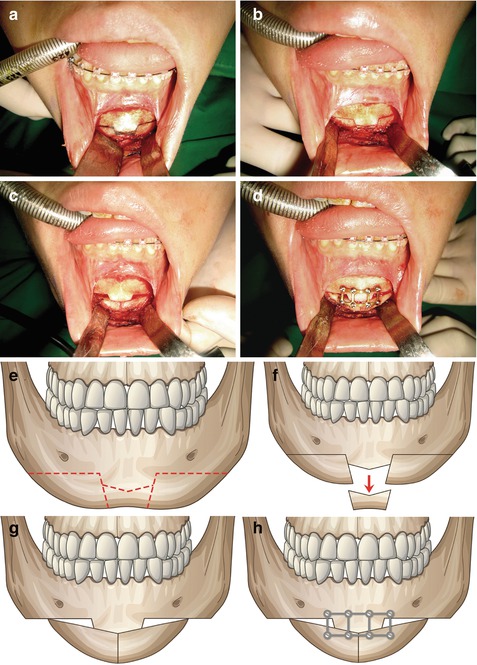

Fig. 8.4

Operative procedures of genioplasty. (a) Labial incision is made at least 5–6 mm inferior to the sulcus avoiding division of the frenulum. (b) The mandible is exposed below the mental foramen and lateral along the inferior mandibular border. (c) Horizontal osteotomy is made with a reciprocating saw. (d, e) Distal bone segment is mobilized according to the preoperative plan. (f) Fixation is done with plate and screws

Fig. 8.6

Operative procedures of lengthening genioplasty. (Left) (a) A horizontal osteotomy line and two vertical osteotomy lines are designed with a small segment left in the center. (b) Osteotomies are carried out with a reciprocating saw. (c) After removing the distal bone segment in the midportion, the two lateral bony segments are approximated in the center. (d) Bone segments are fixed with a microplate and screws. (Right) Illustration of operative desing. (e) Bony design. (f) Central bony segment is removed. (g) Lateral segment is approximated. (h) Fixation is done with microplastes